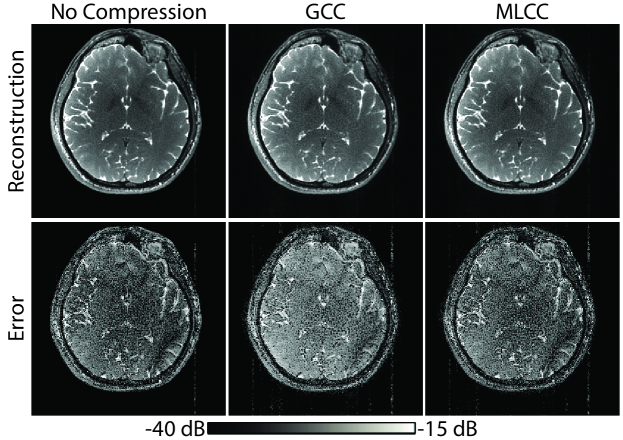

Next, the proposed coil compression –MLCC– was demonstrated on multi-coil data with D=32. Figure 6 displays the proportion of variance that is captured by =6 virtual coils, and the average correlation coefficient between pairs of virtual coil images for a representative subject. MLCC slightly improves variance explained in virtual coils compared to GCC. Furthermore, it increases the amount of shared information across acquisitions captured in coil-compressed data. This can be confirmed visually by virtual coils shown in Sup. Fig. S5. While coil sensitivities based on GCC vary substantially among acquisitions, MLCC yields more consistent coil sensitivities. Note that each acquisition in MLCC-based coils still shows intensity modulation due to bSSFP profiles. These results are valid in each individual subject. Because ReCat leverages an interpolation kernel to synthesize unacquired data across coils and acquisitions, consistency of virtual coils should enhance interpolation performance.

ReCat reconstructions and respective error maps following GCC and MLCC with =6 virtual coils are displayed in Fig. 7. For SPIRiT, PE-SSFP and ReCat, MLCC enables substantially reduced errors compared to GCC, as it increases the amount of information in virtual coils that is shared across multiple acquisitions. Quantitative assessments of coil-compressed ReCat reconstructions are listed in Table 3 for N=2-8, R=4-16, and =6. A comprehensive list of measurement for various reconstruction methods is in Sup. Table S5. For ZF, MLCC and GCC show no significant differences since they account for similar proportion of variance in coil data. For SPIRiT, PE-SSFP and ReCat, MLCC yields higher PSNR than GCC for all N and R (p0.05, sign-rank test). On average, MLCC improves PSNR by 0.80.6 dB over GCC for ReCat (meanstd across subjects; average for N=2-8, R=4-16).